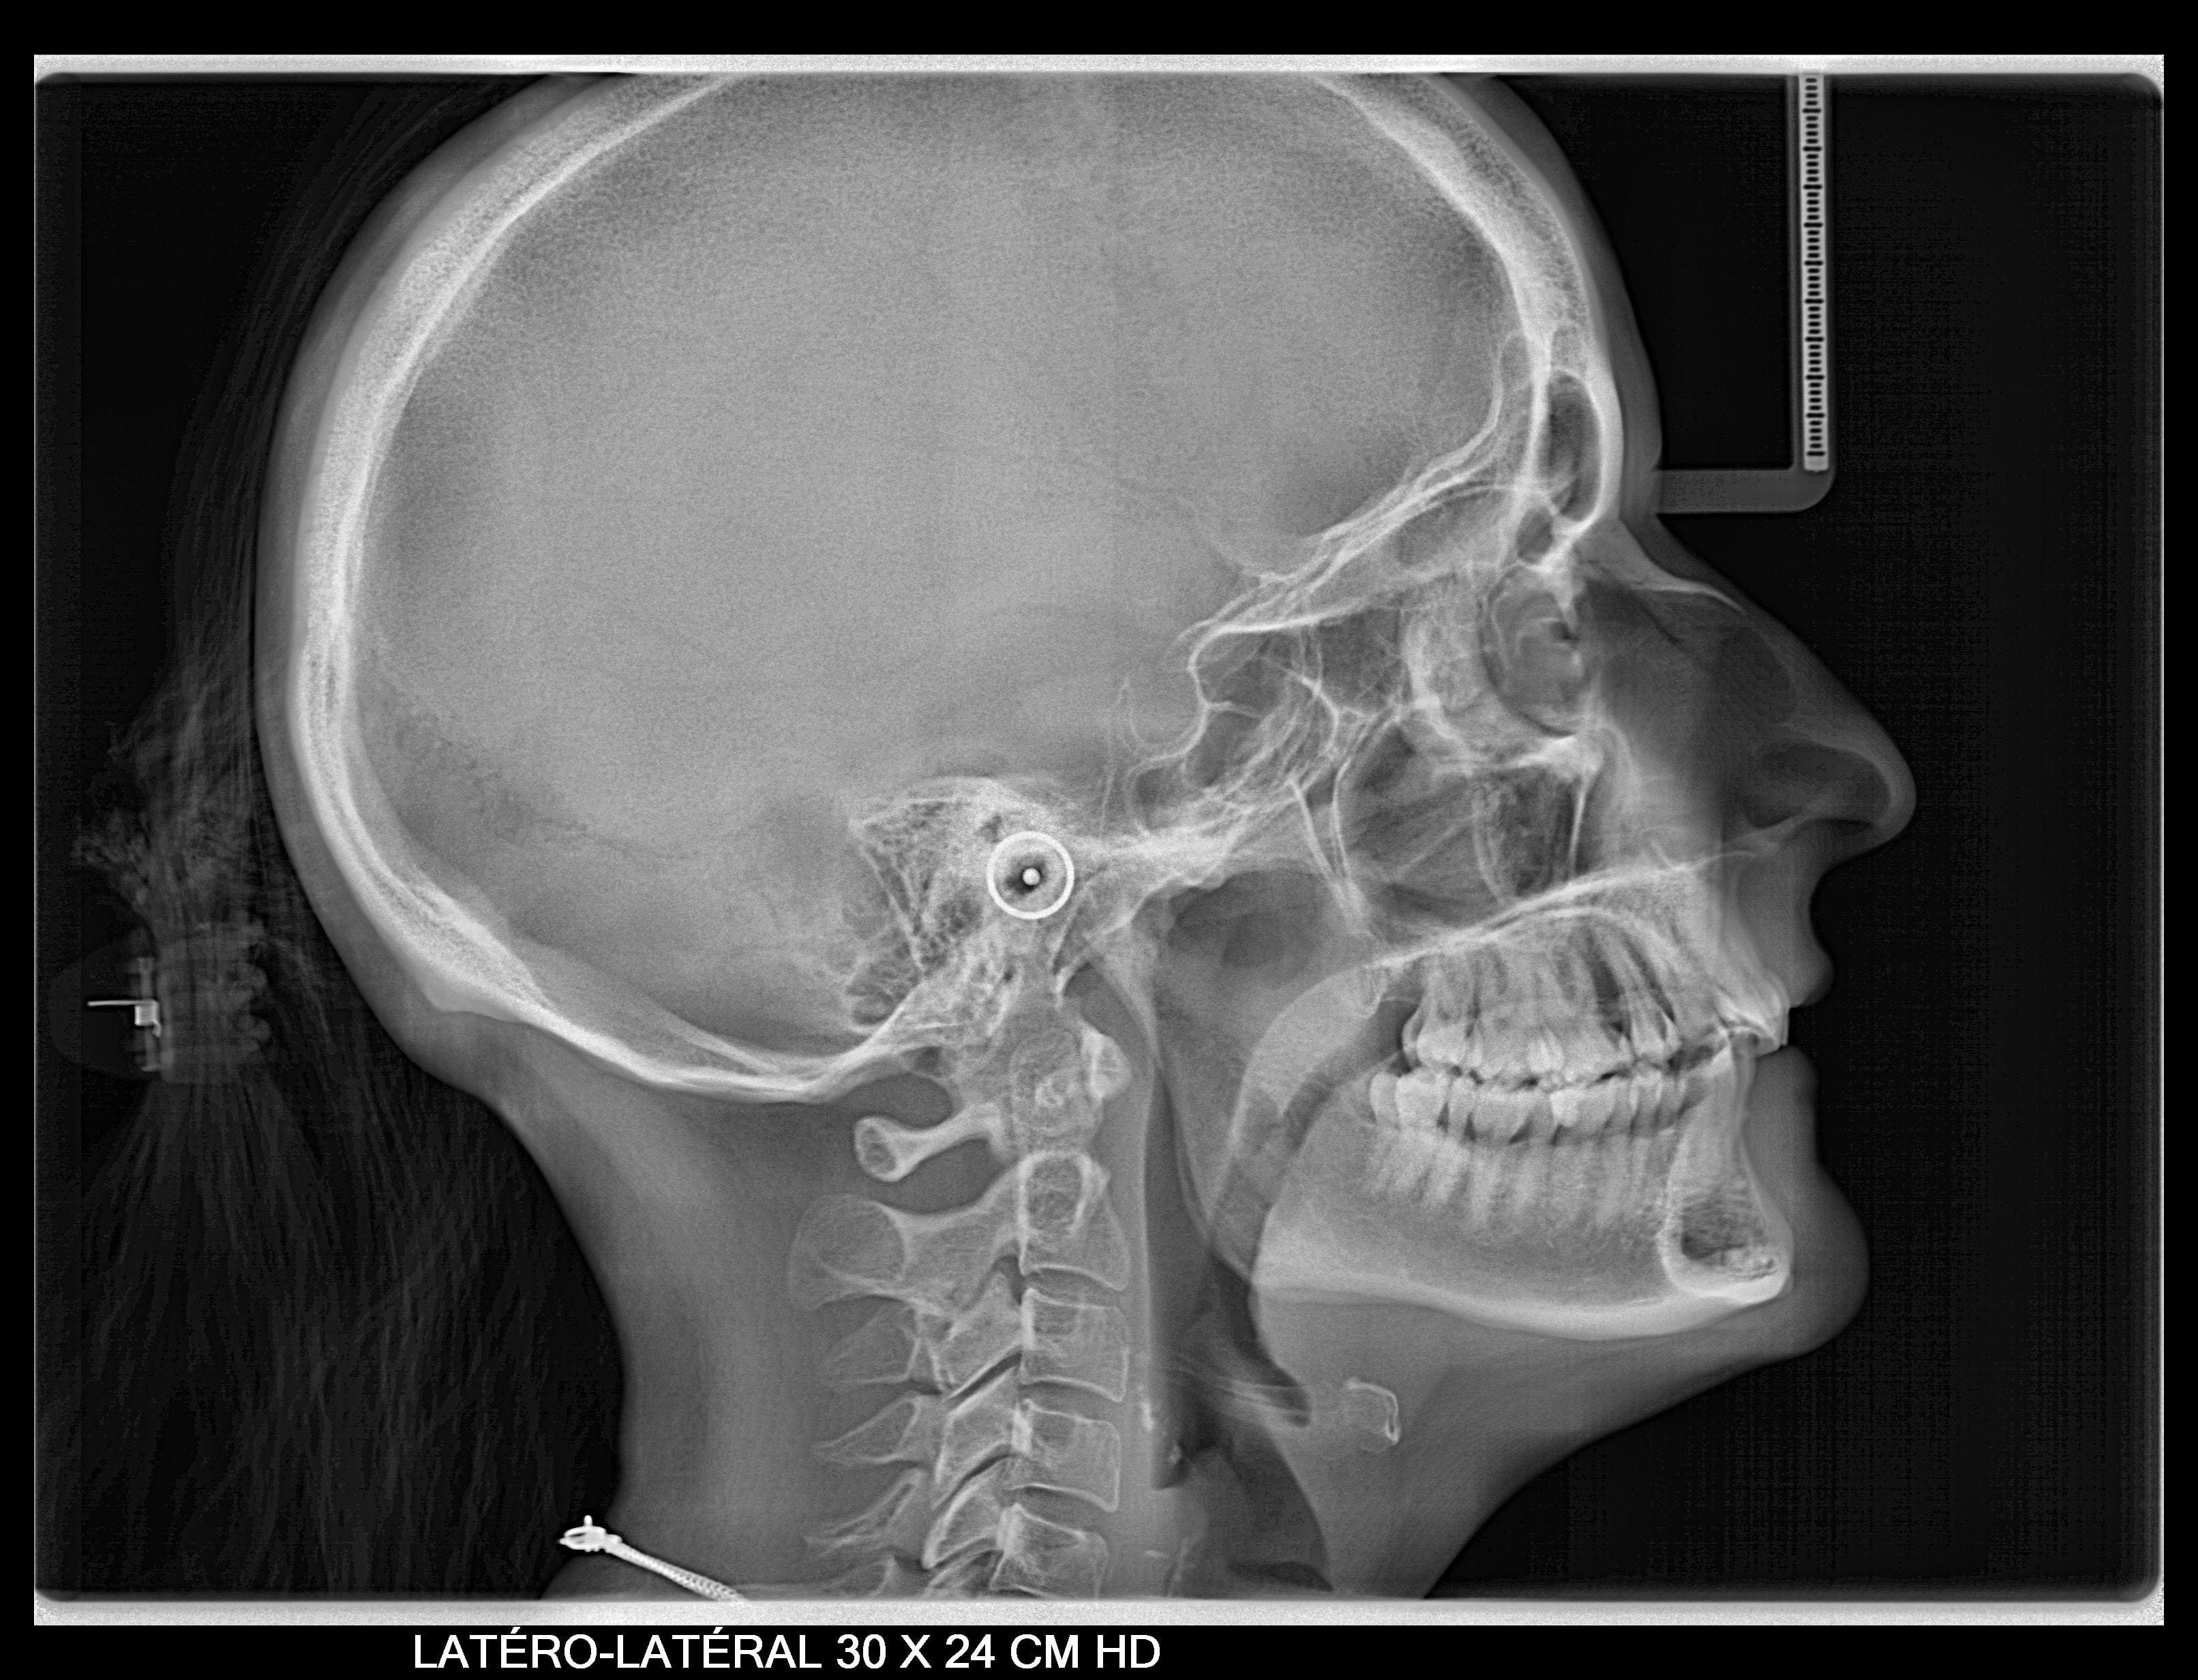

Se obtiene una imagen radiografía del perfil del paciente, del cráneo y las estructuras óseas de la cara, también de tejidos blandos. Fundamental para:

- Los estudios de ortodoncia y cirugía maxilofaciales, ya que permiten medir los ángulos y proporciones de los huesos de la cara del paciente y de este modo conocer la relación entre sus estructuras faciales. También conocidas como cefalometrías.

Puede seleccionarse el área de escaneo horizontal entre tres longitudes distintas de 18, 24 o 30 cm de altura completa (24 cm) o altura reducida (18 cm).